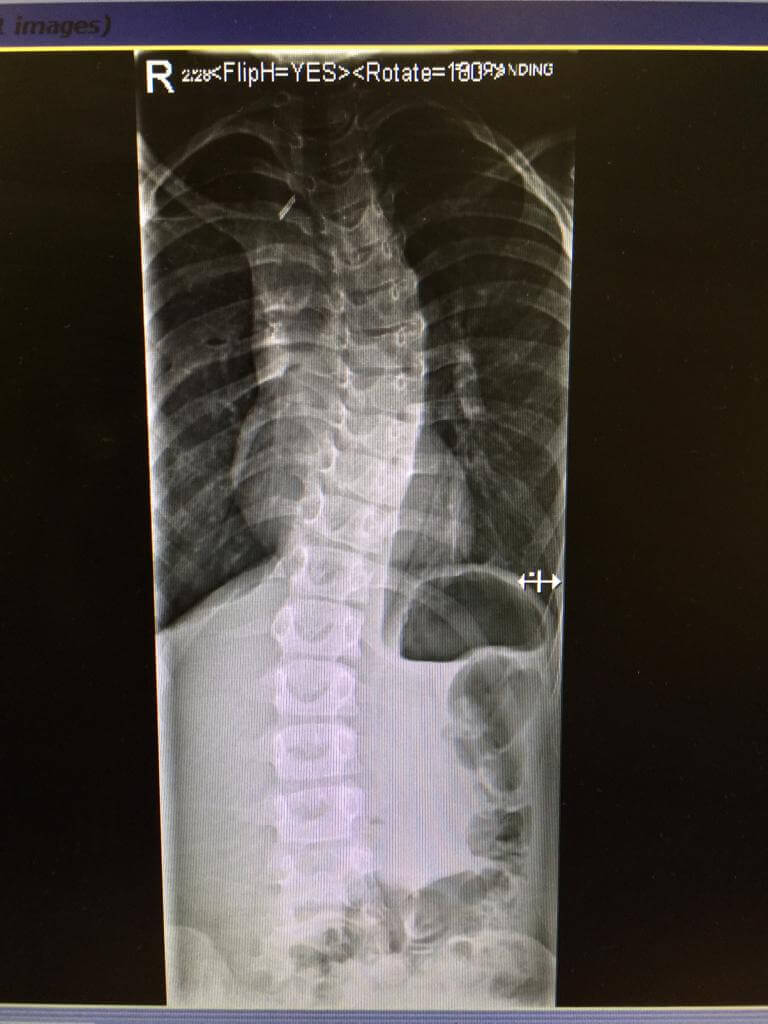

This patient has been seen by ScoliosisUK ltd Physiotherapist since 2013 when the patient was just 6 years old. This is not an idiopathic case – this is a non-idiopathic case – the cause is thought to be a post-operative rib fusion on the right side causing a large left thoracic curve on the left. The original cobb angle was around 50 degrees, and the family were desperate for this patient, who already had complex surgery as an infant, obviously wanted to avoid growing rods or fusion. This patient was provided with a NHS Boston and Cheneau derivatives initially and then finally several Gensingen Cheneau brace from 2016 and has managed to avoid surgery – now she is 15 years old with a 35-degree thoracic cobb angle. It’s been a tricky case as the consultant surgeon did not want to separate the ribs, which would have allowed for more cobb angle correction as the fusion of ribs prevents this, but this girl is a fighter, and she is now becoming a thriving young woman. She has had sharp bursts of support Schroth Best Practice home programs over the years in 6-12 week amounts to help with her shortened muscles and scar tissue, mum and dad both supportive. Her final Gensingen brace is being fitted shortly and we hope to see further signs of maturity on her X-ray to allow for part time hours this year, we all have everything crossed to see bony maturity and allow more weaning from brace sometime soon.

‘Non-idiopathic case – 6-year-old juvenile scoliosis thought to be a consequence of previous surgery and ultimately ribs fusing together. She reversed the curve from above 50 to 39 degrees cobb angle and holding strong at age 15’